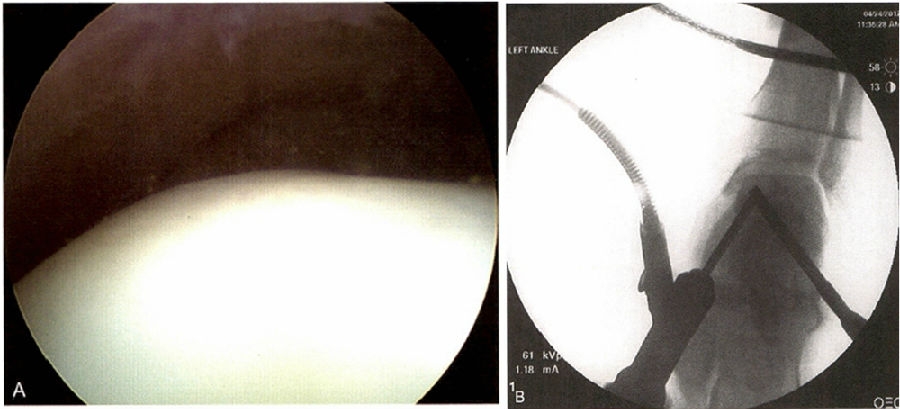

无论在开放手术还是在关节镜手术中,目前最佳的技术还是对关节缺损面的清创和钻孔。经踝钻孔(近端至远端钻孔)可以通过关节镜监视或经皮增强造影检查辅助完成。胫骨远端骨骺未闭合时要避免穿骺板的多次钻孔。